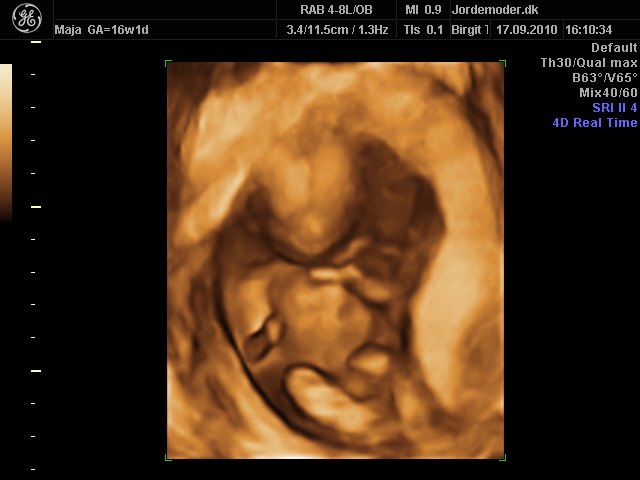

billede 5 - 16+1 3d